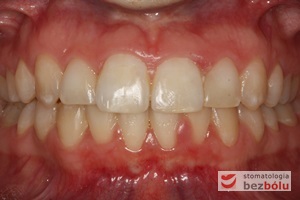

Leczenie bezekstrakcyjne z wykorzystaniem strippingu

Pacjentka lat 22 zgłosiła się do naszej placówki celem podjęcia leczenia ortodontycznego. Głównym oczekiwaniem pacjentki była poprawa estetyki uśmiechu oraz brak ekstrakcji zębów na drodze do jej uzyskania. Ze względu na liczne stłoczenia zębów w górnym i dolnym łuku, dość duży materiał zębowy w porównaniu z bazą kostną, a także zgryz przewieszony boczny prawostronny po dokładnej analizie cefalometrycznej oraz analizie modeli diagnostycznych zastosowano leczenie bezekstrakcyjne z wykorzystaniem strippingu jako alternatywy dla usuwania zębów, mającego na celu uzyskanie miejsca w łuku na uszeregowanie zębów. Po fazie aktywnego leczenia trwającego 18 miesięcy zastosowano leczenie retencyjne w postaci szyny retencyjnej w łuku górnym oraz retainera stałego w łuku zębowym dolnym klejonego od kła do kła.